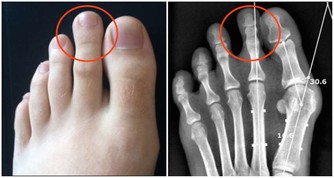

人體十二經脈的起點或終點都在身體末梢,其中六條走到雙手,停在十根指頭,打開手心有三條陰經走到大拇指、中指、小姆指翻到手背則有三條陽經走到食指、無名指、小姆指,而另外六條通達腳趾的經脈也可以透過相似的經氣,在手上得到表裡的對應。

雙手匯通全身經脈,

循著連接手指的六條經絡及其相應經氣,大拇指的少商穴對應肺、脾食指的商陽穴對應大腸、胃中指的中沖穴對應心包、肝無名指的關沖穴對應三焦、膽小指的少澤穴對應心、腎少沖穴對應小腸、膀胱。